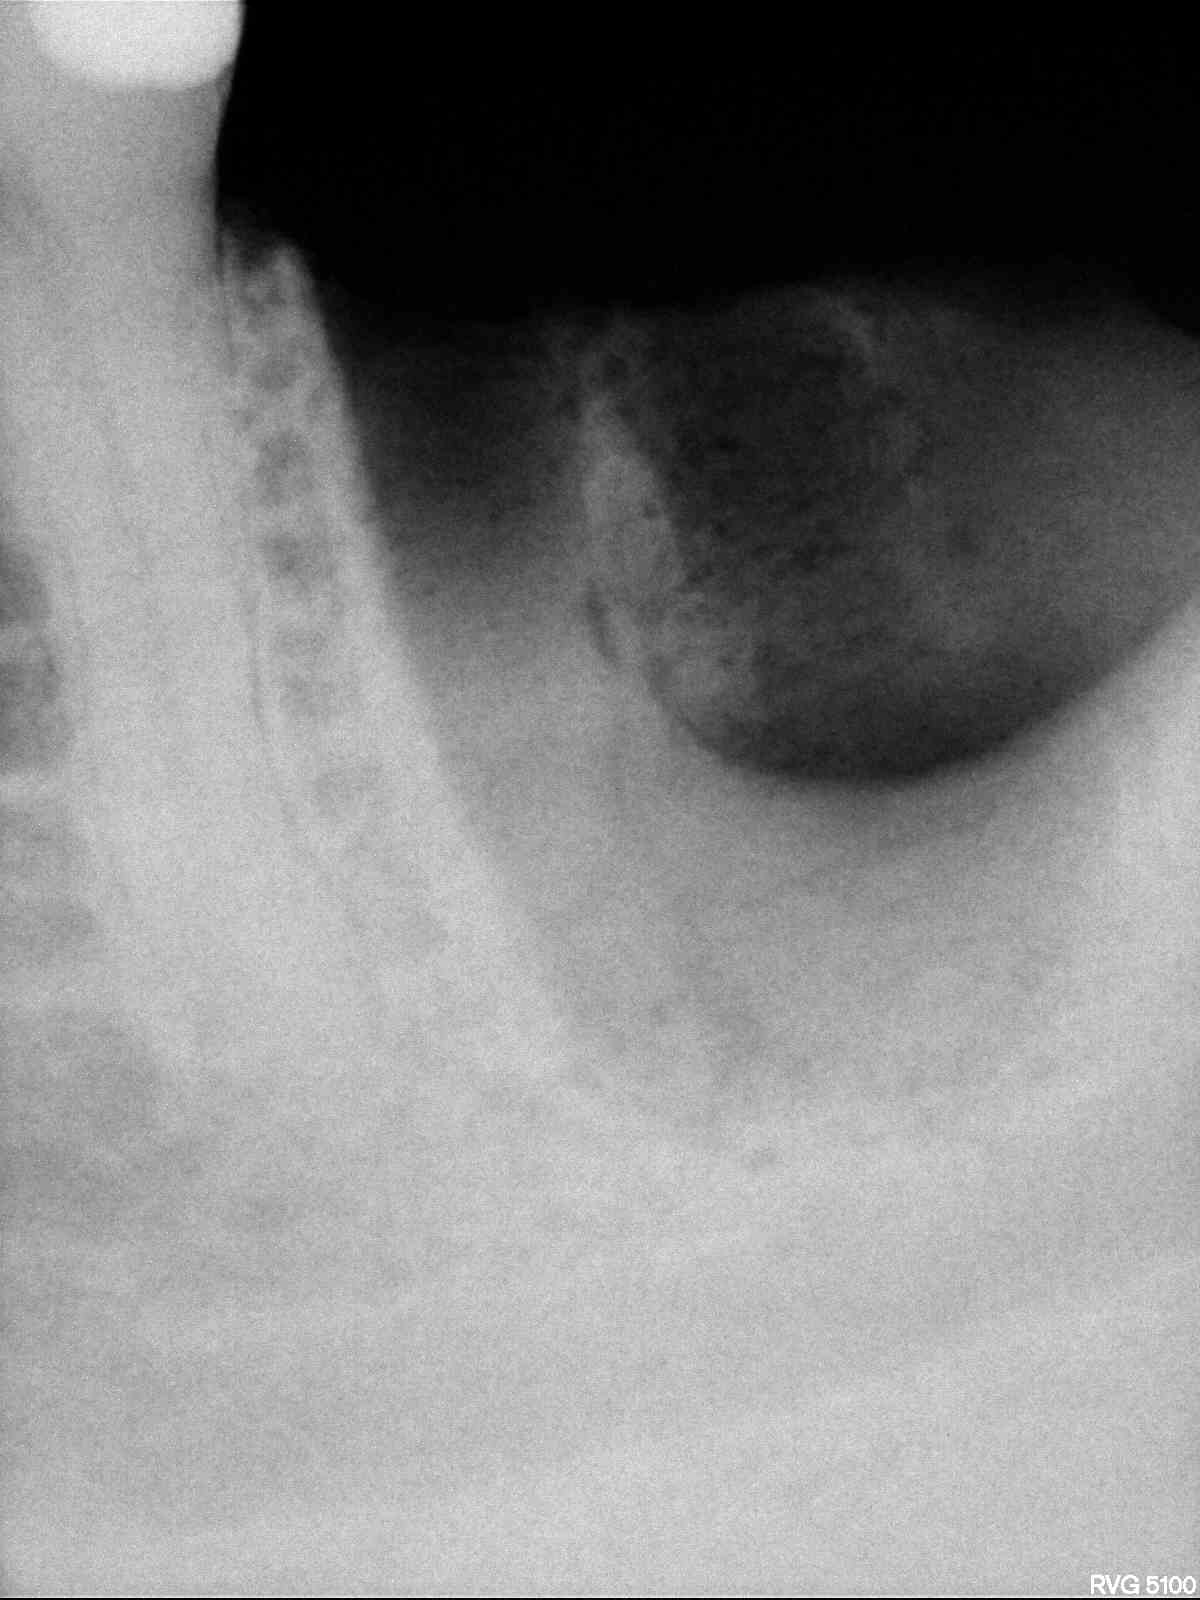

Radios1 dxb8my - Eugenol

Radios2 kprrcu - Eugenol

Radios3 auio0x - Eugenol

Radios4 pfsefa - Eugenol

Radios5 uwurgt - Eugenol

Radios6 ycayfo - Eugenol

Des inlay core... Des endos moisies... C est un français.

Ah ? C'est un français il a des inlay cores et des endos pourries. Ca réduit considérablement les recherches. -))))

maladie dentaire diffuse + antécédent de choc (11 racine fracturée)